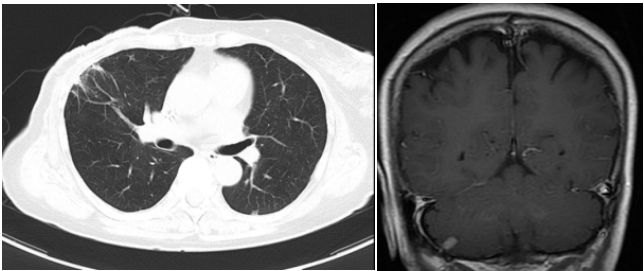

④三线治疗:曲妥珠单抗(汉曲优) 300mg Q3W+吡咯替尼 320mg QD+唑来膦酸4mg Q3M,并予以局部区域放疗。维持治疗至2022.03.31出现新发左肺转移灶及右侧小脑转移灶。行支气管镜检查,并取左肺下叶背段支气管开口见新生物活检,病理提示:(左肺结节)乳腺癌转移,Ki-67(20%,+),ER(-),PR(-),HER2(3+)。右侧小脑异常信号,1.2cm(图5),考虑转移。疗效评价PD,PFS 16个月。

图5. 2022.03左肺及右侧小脑影像图

⑤四线治疗:T-DM1 180mg Q3W;

两个疗程后评估:左肺下叶转移灶较前缩小,1.1cm;右侧小脑转移灶较前缩小,0.8cm(图6)。疗效评价 PR,继续维持该方案。

图6. 2022.05左肺及右侧小脑影像图